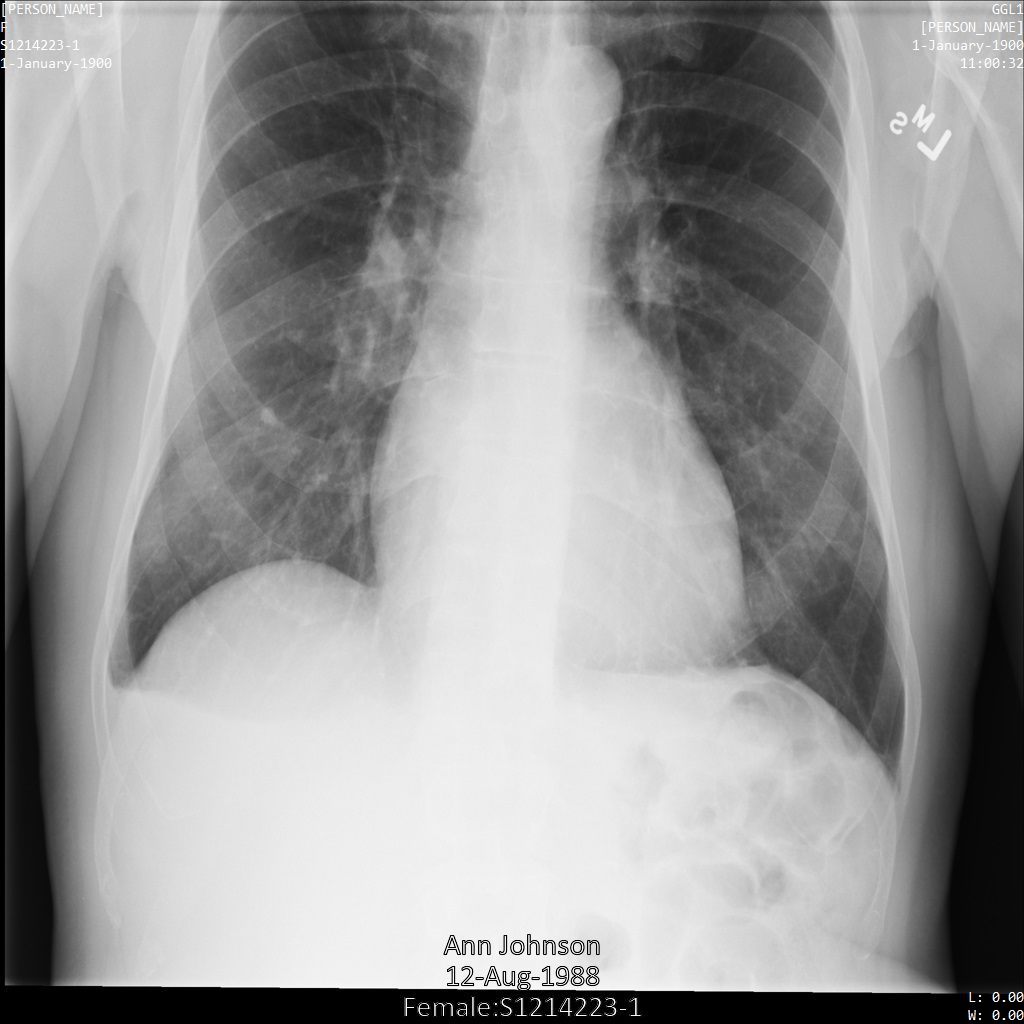

Chacune des sections suivantes fournit des exemples d'anonymisation de données DICOM à l'aide de différentes méthodes. Une sortie de l'image anonymisée est fournie avec chaque échantillon. Chaque exemple utilise l'image d'origine suivante comme entrée :

Vous pouvez comparer l'image de sortie de chaque opération d'anonymisation à cette image d'origine pour voir les effets de l'opération.

L'image suivante montre une radiographie non masquée d'un patient :